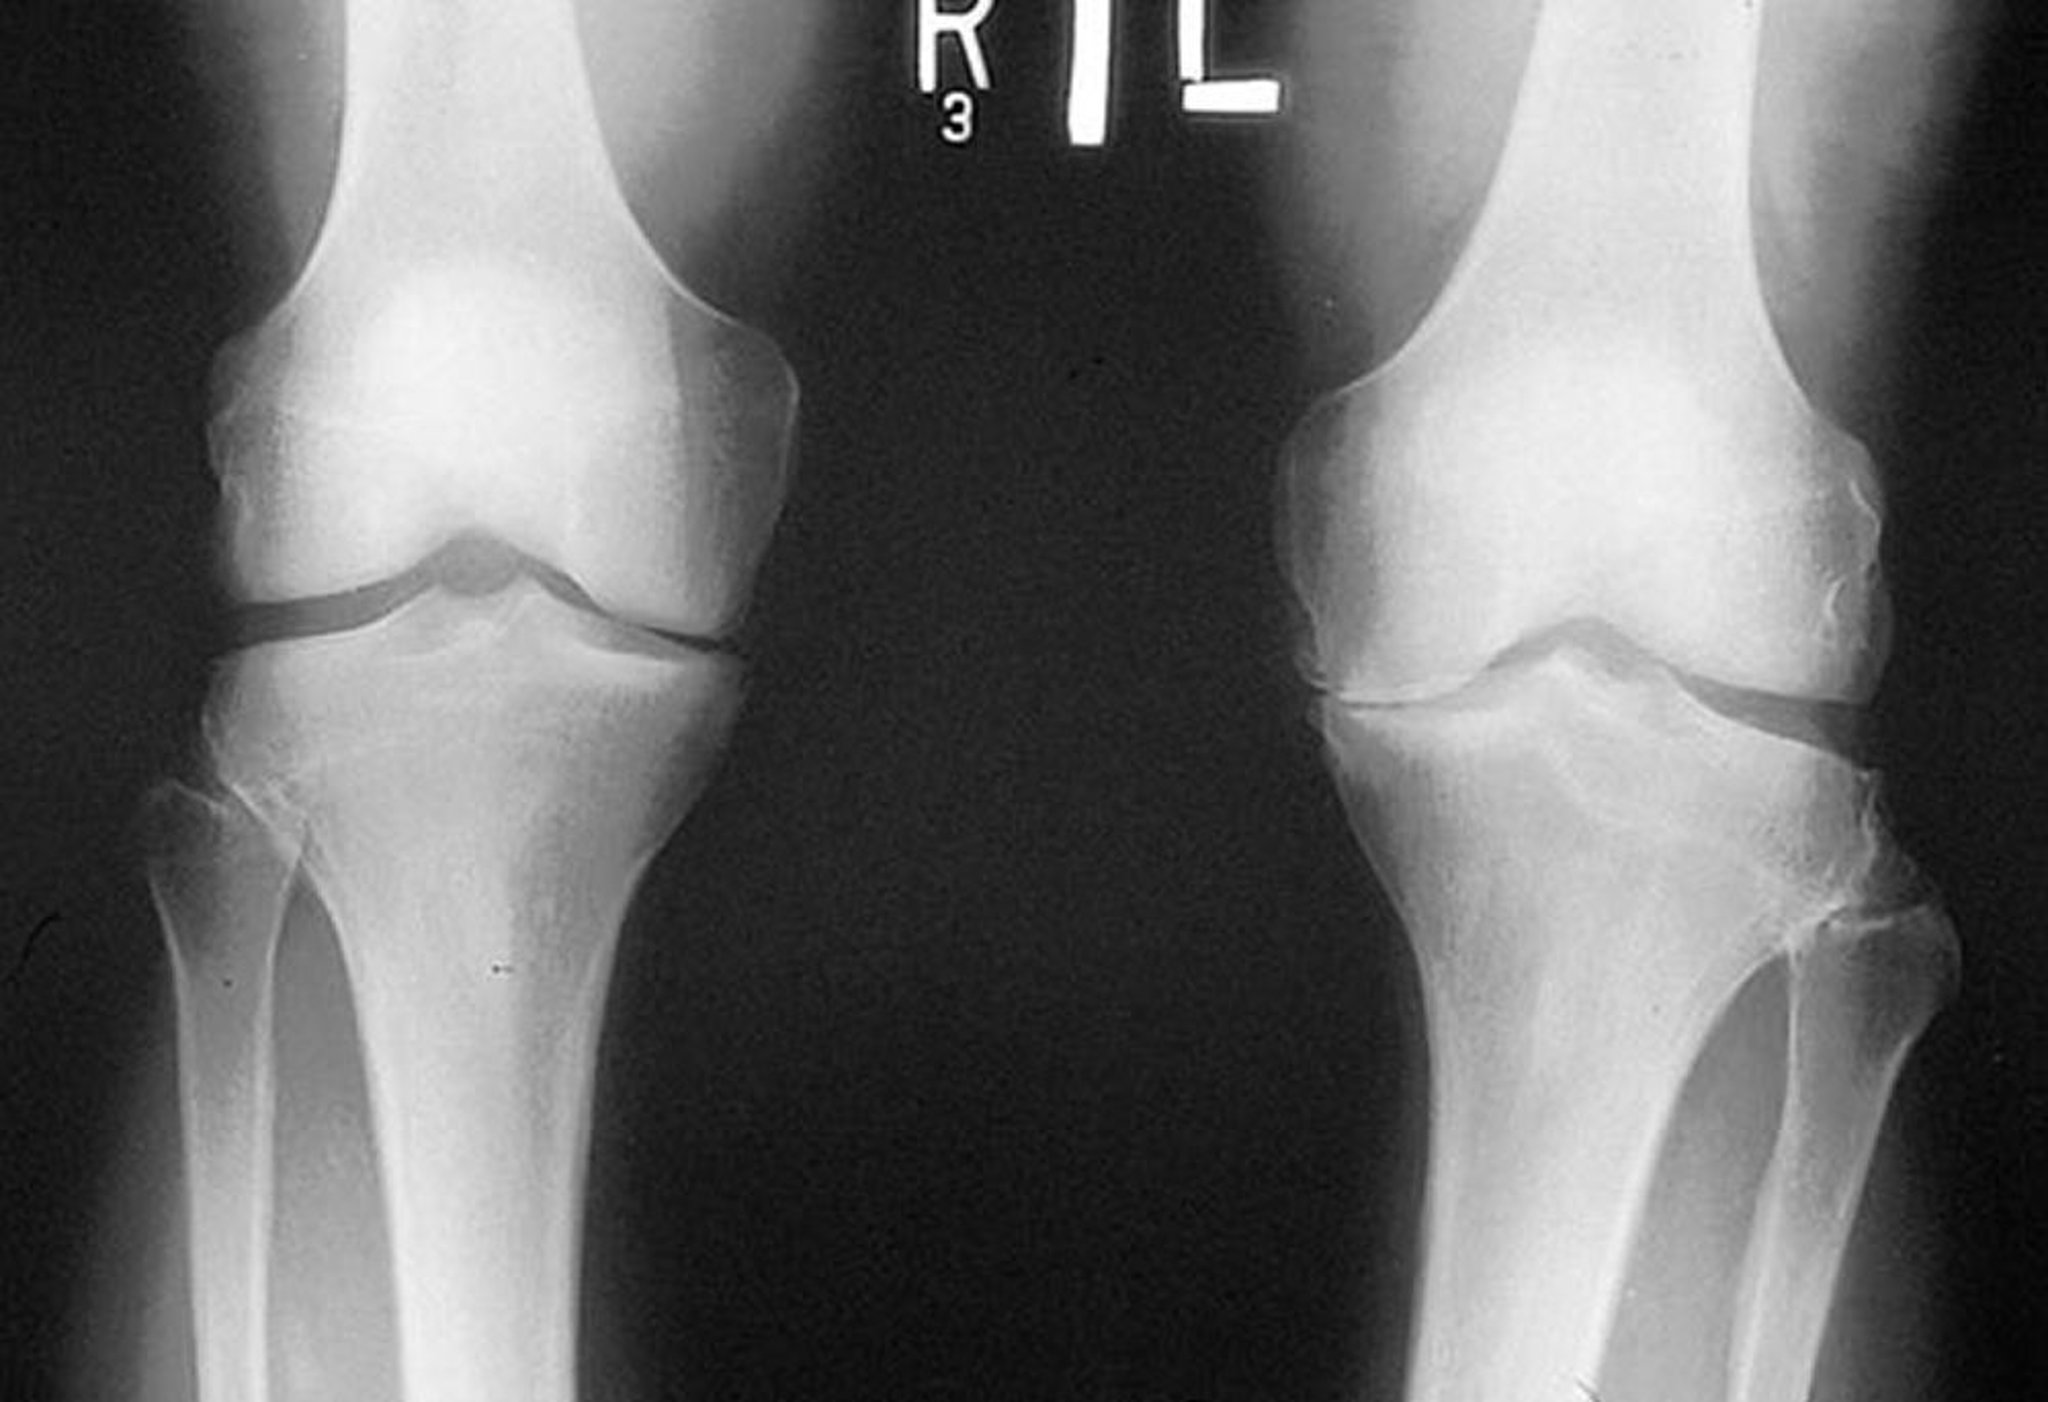

This radiograph, taken while the patient is standing, shows that the tibiofemoral joint space in the medial compartment of both knees is narrow, particularly on the left. Marginal osteophytes are visible. There is attrition of the left medial tibial plateau.

By permission of the publisher. From Myers S: Atlas of Rheumatology. Edited by G Hunder. Philadelphia, Current Medicine, 2005.

Osteoarthritis should be suspected in patients with gradual onset of symptoms and signs, particularly in older adults. If osteoarthritis is suspected, radiographs should be taken of the most symptomatic joints. Radiographs generally reveal marginal osteophytes, narrowing of the joint space, increased density of the subchondral bone, subchondral cyst formation, bony remodeling, and sometimes joint effusions. Standing weight-bearing Merchant view (tangential view with knee flexed 30°) radiographs of the knees are more sensitive in detecting joint space narrowing. Discrepancy between severity of symptoms and severity of changes in imaging is common (1).